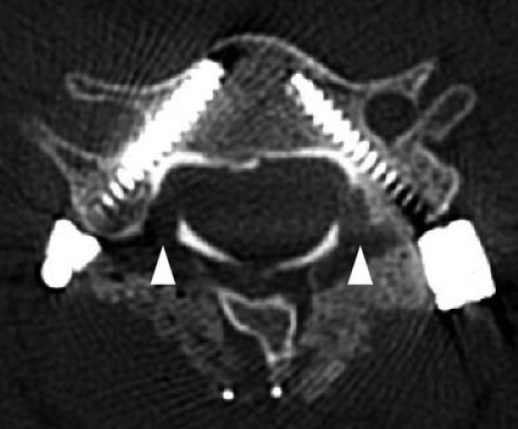

(2)俯卧位,常规后路显露,骨膜下剥离软组织至侧块关节外缘。于侧块关节内缘与椎板交接开窗,探查椎弓根内壁。(以C5右侧CPS螺钉置入为例,右侧为头端)

(3)经开窗根据神经钩探查的椎弓根内壁位置,在直视下置入CPS。

(4)术中全程无透视完成置钉,术后复查CT观察CPS螺钉位置。本例与术前规划一致,白色三角形箭头所示两侧探查椎弓根于椎板开窗位置。